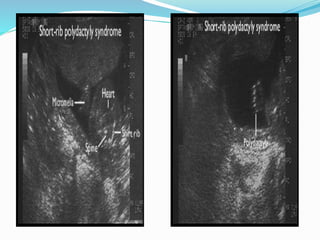

Short ribbed polydactyly

Syndromes

 Small Narrow thorax + short limbs + polydactyly +

specific feature for each type

 Type 1 : (SALDINO- NOONAN Syndrome)

- Micromelia with pointed ends in long bones

- Urogenital and anorectal anomalies

 Type 2 (MAJEWKSKI SYNDROME)

- Median cleft lip/palate and disproportionally

short tibiae

Prongnosis

 LETHAL Secondary to respiratory faliure

Short ribbed polydactyly Syndromes Small Narrow thorax + short limbs + polydactyly + specific feature for each type  Type 1 : (SALDINO- NOONAN Syndrome) - Micromelia with pointed ends in long bones - Urogenital and anorectal anomalies

 Type 2(MAJEWKSKI SYNDROME) - Median cleft lip/palate and disproportionally short tibiae

Prongnosis  LETHAL Secondaryto respiratory faliure